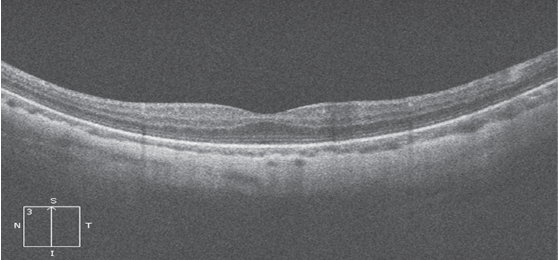

Куполообразная макула была впервые описана французским офтальмологом D. Gaucher et al. в 2008 г. как выпуклый выступ макулы внутри стафиломы у пациентов с высокой миопией [14]. Данное явление было диагностировано с помощью оптической когерентной томографии высокого разрешения (EDI-OCT) и было неожиданным, так как при миопии высокой степени мы обычно встречаемся с удлинением и растяжением оболочек глаза, в данном же случае определяется локальное утолщение склеры в области макулы с формированием купола (рис. 1).

Рис. 1. Томограмма макулярной зоны сетчатки при миопии высокой степени (Optovue RTVue XR 100 Avanti). На поперечном срезе хорошо визуализируются наружные и внутренние слои сетчатки. Контрастная линия пигментного эпителия куполообразно приподнята, под ней виден неравномерный по толщине слой сосудов хориоидеи (короткая линия) с выраженным утолщением склеры под ним (длинная линия)

На поперечном срезе хорошо визуализируются наружные и внутренние слои сетчатки. Контрастная линия пигментного эпителия куполообразно приподнята, под ней виден неравномерный по толщине слой сосудов хориоидеи с выраженным утолщением склеры под ним. В то же время при типичной миопии высокой степени данные оптической когерентной томографии (ОКТ) выглядят иначе (рис. 2).